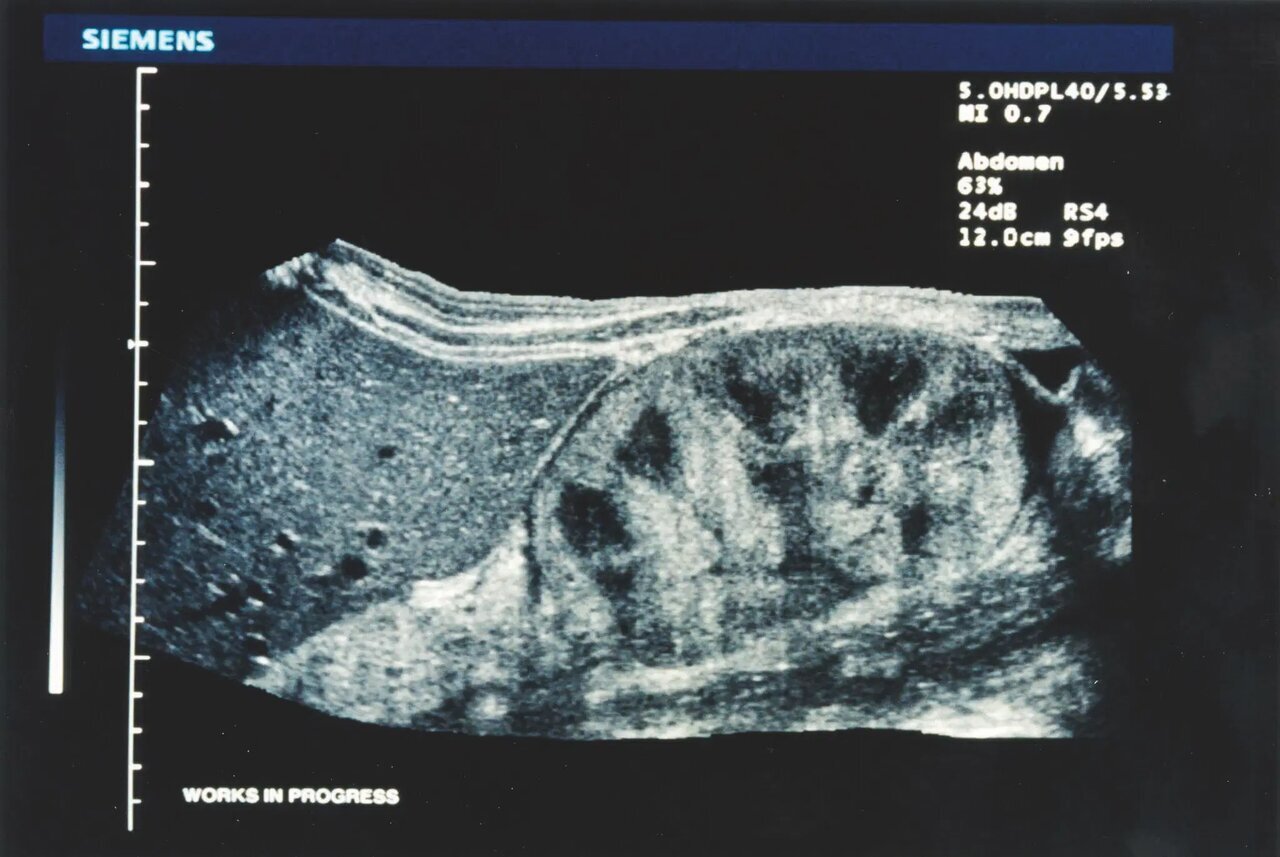

نرمافزار SieScape که به طور کامل در دستگاه سونوگرافی پیشرفته SONOLINE Elegra ادغام شد، برای اولین بار در سراسر جهان به کاربران این امکان را داد که فوراً ساختارها و اندام های داخلی تا ۶۰ سانتی متر عرض را با یک واحد اولتراسوند با وضوح بالا در یک تصویر مشاهده کنند.

تصاویر با یک کاوشگر استاندارد بدون سنسور موقعیت به دست میآمد و پزشک را قادر میساخت تا با حرکت دادن پروب بر روی سطح بدن، مقاطع عرضی را بدست آورد.